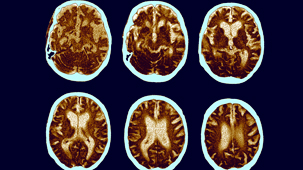

Thanks to the introduction of a range of non-invasive brain imaging techniques, neurosurgical procedures in particular have been revolutionised.

Electroencephalography, Functional Magnetic Resonance Imaging and other machines have increased our knowledge of the brain's inner workings.

Functional Magnetic Resonance Imaging (FMRI) and magnetoencephalography (MEG) have become essential tools for investigating the brain. Thanks to brain scanning, our knowledge of core physical processes - memory, sight, muscle control - has been hugely improved. But are researchers justified in using these tools to delve into more complex and subjective areas such as emotions, aesthetics and morality? (2009)

Dr Mark Lythgoe investigates the technology of brain scanning. Will this technique ever help people suffering from mental illnesses such as depression and schizophrenia? (2007)

Dr Mark Lythgoe, Director of the Centre for Advanced Biomedical Imaging, tells the untold story of medical imaging and why uncovering our inner selves changed the world. (2010)

In the first of a new series of Frontiers, Peter Evans discusses new research into vegetative state. Scientists at Cambridge University recently published a paper suggesting that there were "islands" of brain function in the brain of a patient in a vegetative state. Using Magnetic Resonance Imaging, the researchers have shown that the patient's brain apparently responded to spoken instructions. (2006)